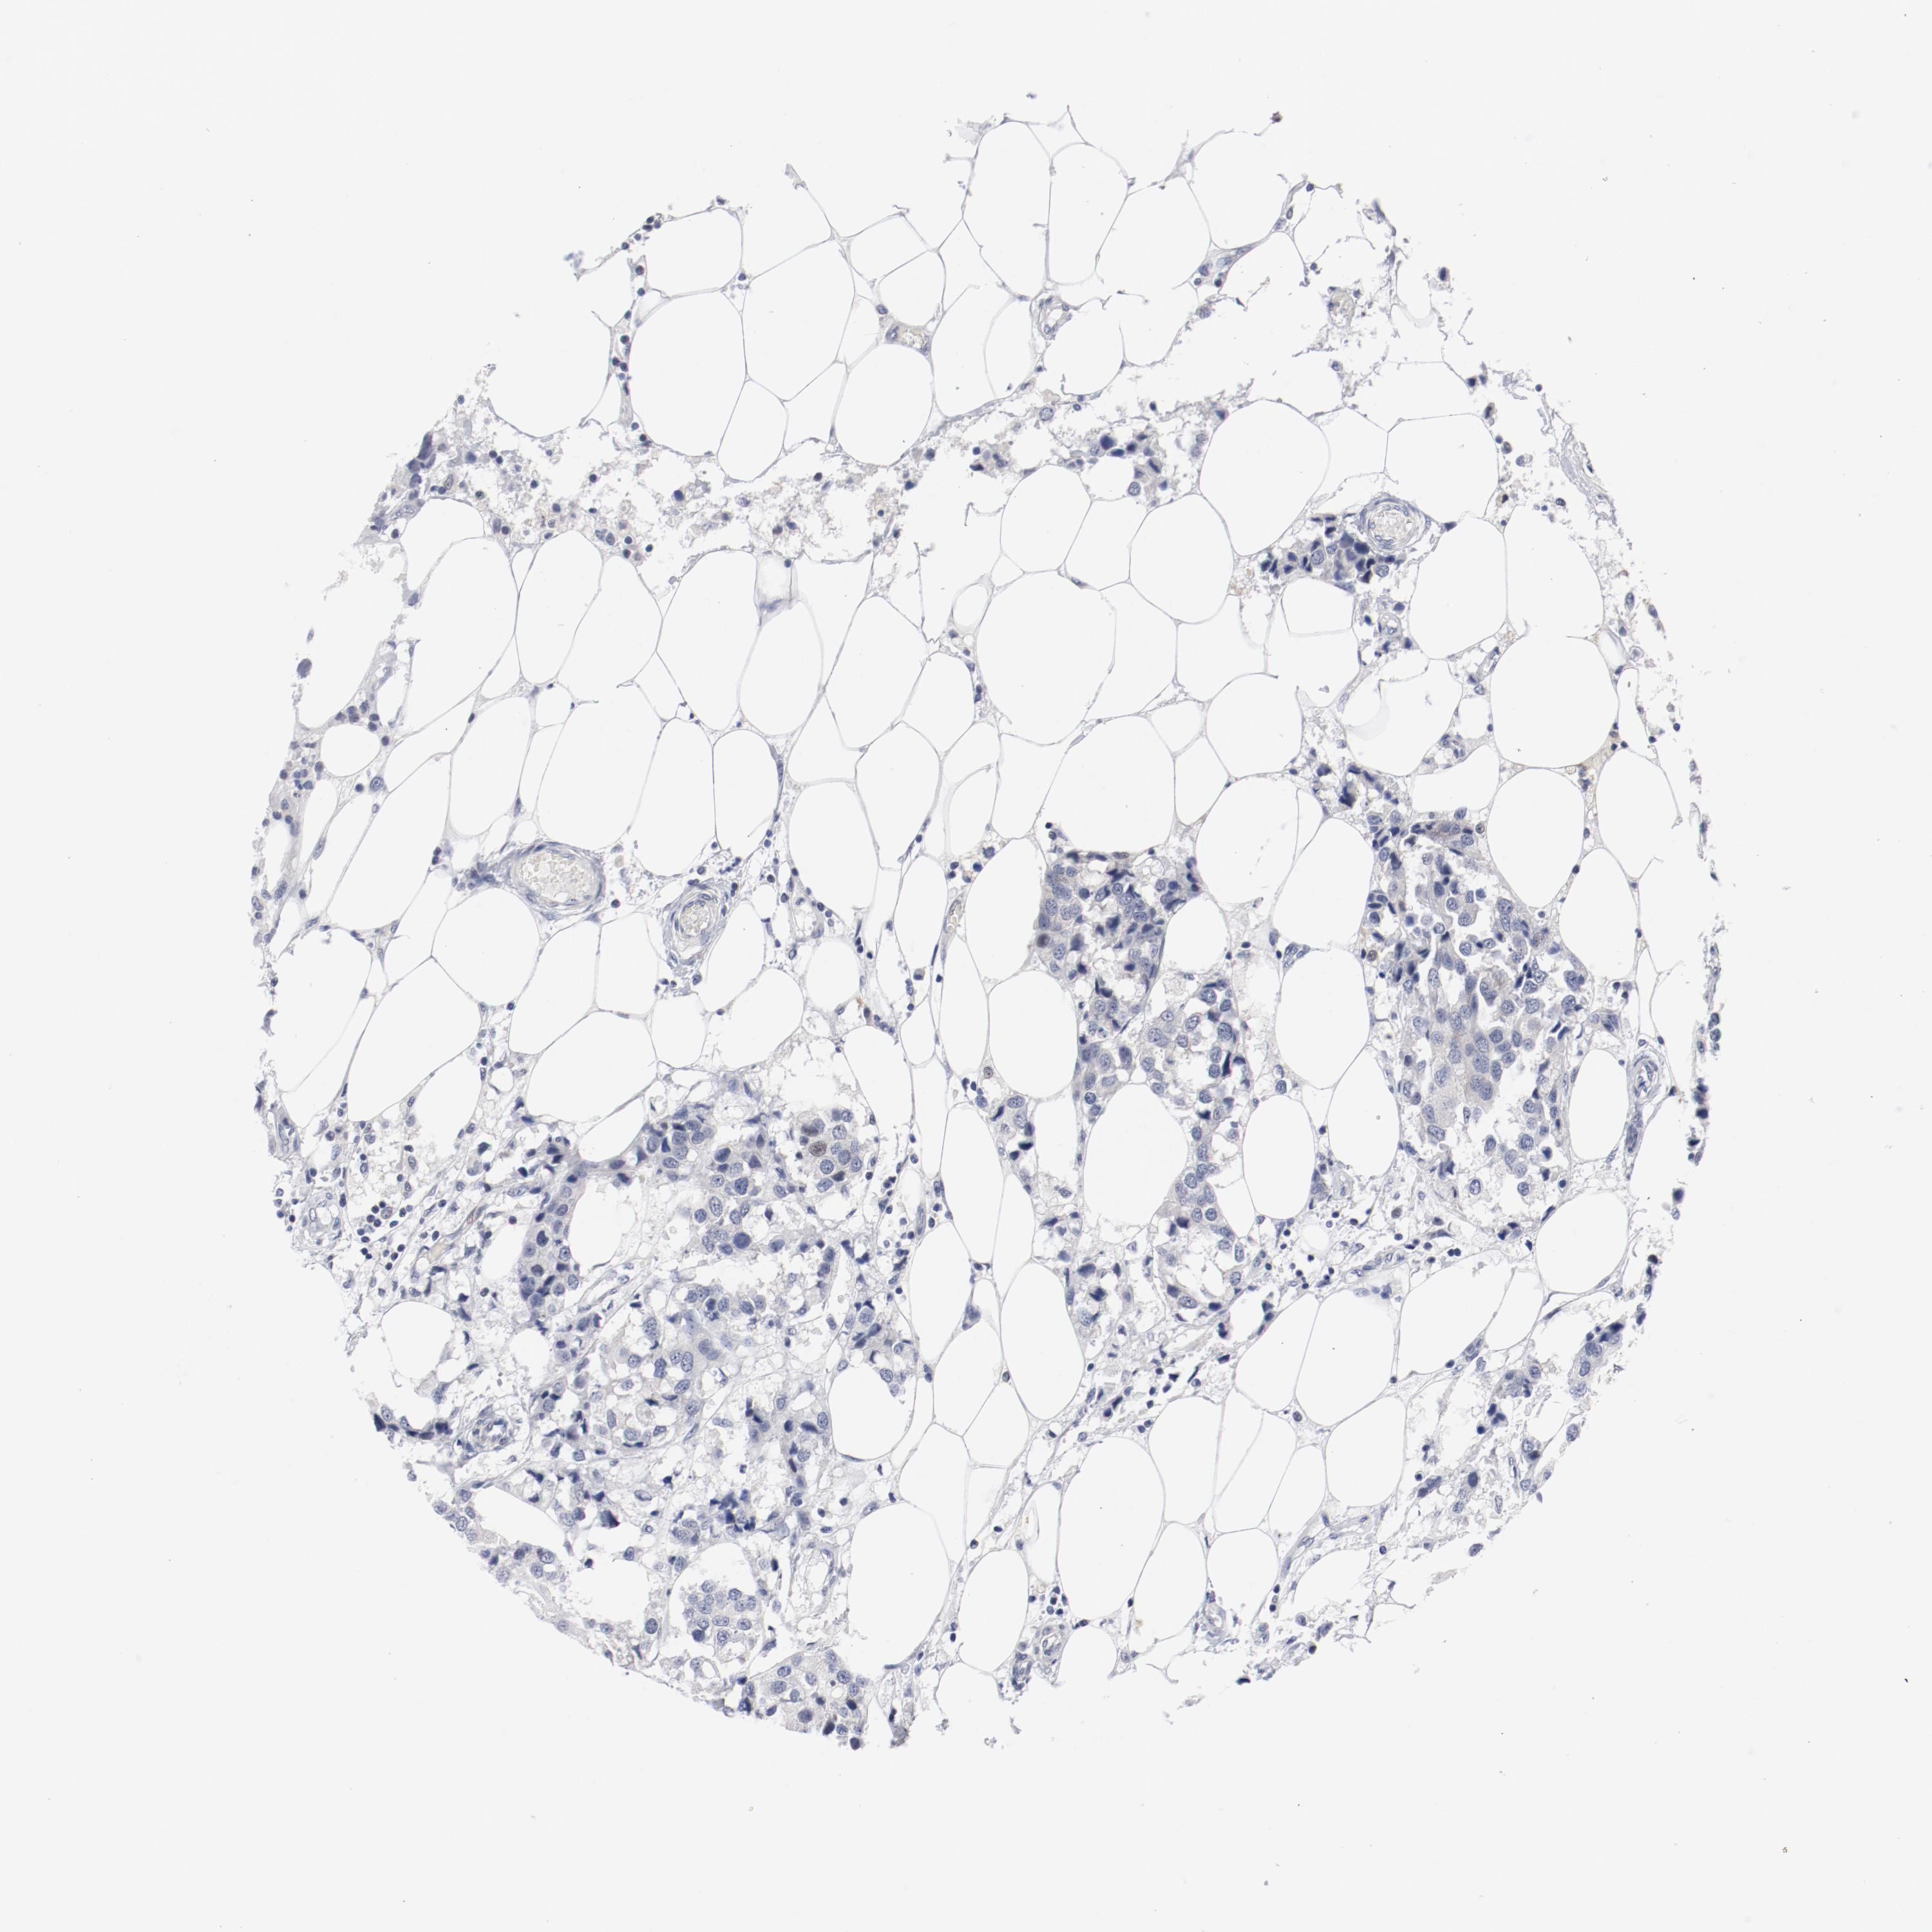

CANCER BREAST CANCER Show tissue menu

BRCA TCGA BRCA VALIDATION PROTEIN EXPRESSION